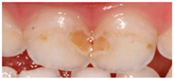

IMAGE 4![]() | Dental caries | 40 (11.1) |

| Enamel defects | 284 (79.1) | |

| No dental lesions | 13 (3.6) | |

| I do not know | 22 (6.1) |

| IMAGE 4 | ||||||

| Enamel defects | 92 (25.6) | 83 (23.1) | 60 (16.7) | 43 (12.0) | 6 (1.7) | p < 0.05 |